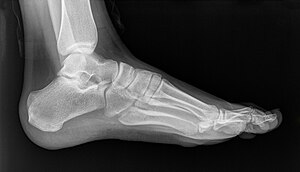

Плоскосто́пие — изменение формы стопы, характеризующееся опущением её продольного и поперечного сводов. Различается поперечное и продольное плоскостопие, возможно сочетание обеих этих форм.

Для диагностики плоскостопия используют данные рентгенографии с рентгенометрией и плантографии при отпечатке подошвы стопы. По выраженности проявлений выделяют три степени продольного и четыре степени поперечного плоскостопия; продольное плоскостопие может сочетаться с любой степенью поперечного плоскостопия. Предварительный диагноз «плоскостопие» может быть выставлен ортопедом на основании физикального осмотра или анализа изображений, полученных при помощи подоскопа или плантографа. Определяются правильность расположения анатомических ориентиров стопы и голеностопного сустава, объём движений и углы отклонения стопы, реакция сводов и мышц на нагрузку, особенности походки, особенности износа обуви[4][2][3].